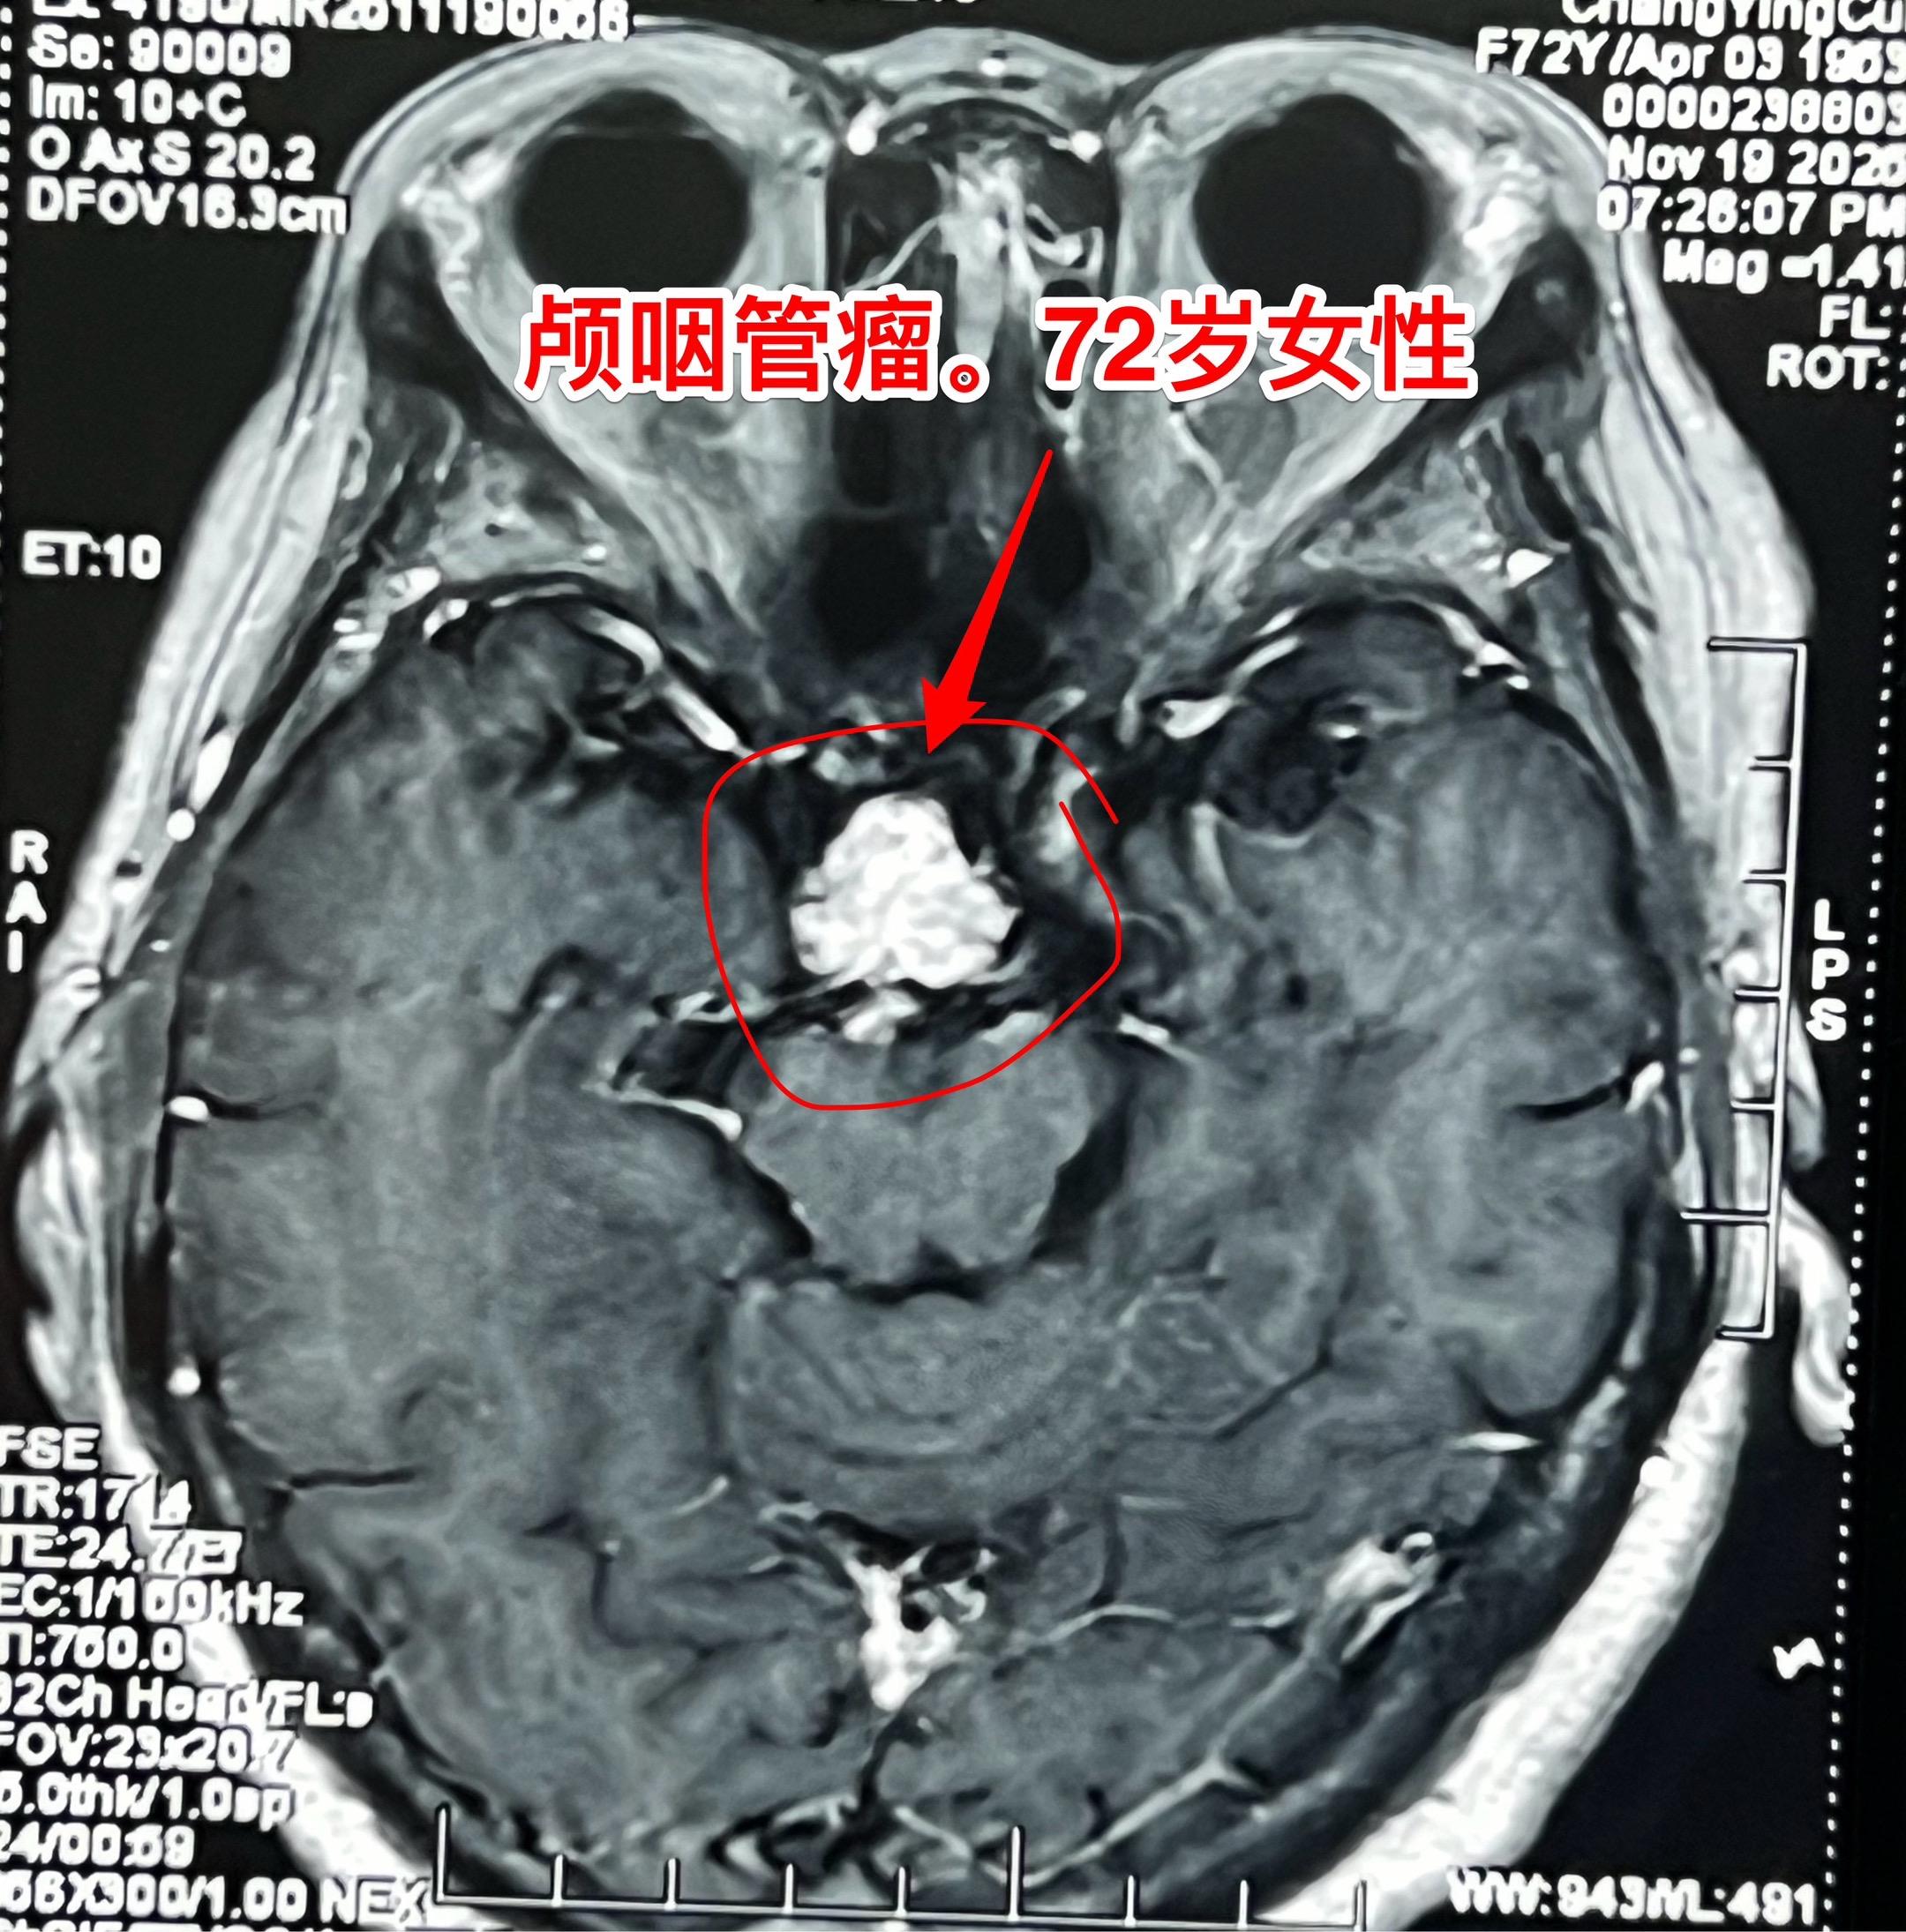

颅咽管瘤可以在任何年龄发病。72岁老人也患颅咽管瘤! 很多人都认为颅咽管瘤是小孩子得的病,其实不然。 70岁以上的老人也会患上颅咽管瘤这种病。这个72岁的青海省女性,因为视力下降、头痛到医院检查,发现了这个颅咽管瘤。 12月5日在我科行开颅手术将肿瘤完全切除。(今年我科的第193个颅咽管瘤手术。